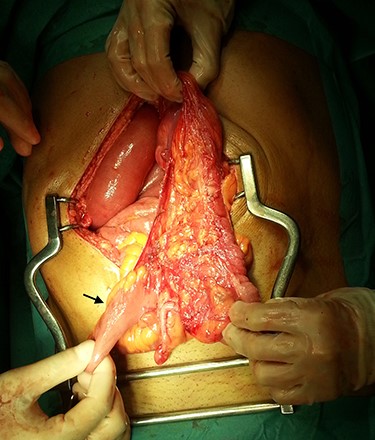

In the presence of an intestinal obstruction of an unclear cause, an exploratory laparotomy was proposed. A peritoneal encapsulation (Fig. 4) of the small bowel was identified, without intestinal ischemia. The peritoneal sac was located in the right abdominal quadrants, only partially involving the small bowel, so in the left quadrants there was normal caliber ileum externally to it. The membrane was excised and the peritoneal cavity was explored, showing signs of intestinal malrotation with medialization of the right colon (Fig. 5) and a retrocecal position of the terminal ileum leading to intestinal obstruction (Fig. 6). After lysis of adhesions from the bowel to the membrane, the terminal ileum was released and complementary appendectomy was done. Histopathology revealed normal peritoneal tissue. After prolonged ileus, patient was discharged on the 8th postoperative day and presented asymptomatic 1 year later.

Terminal ileum in a retrocecal position leading to intestinal obstruction (arrow).